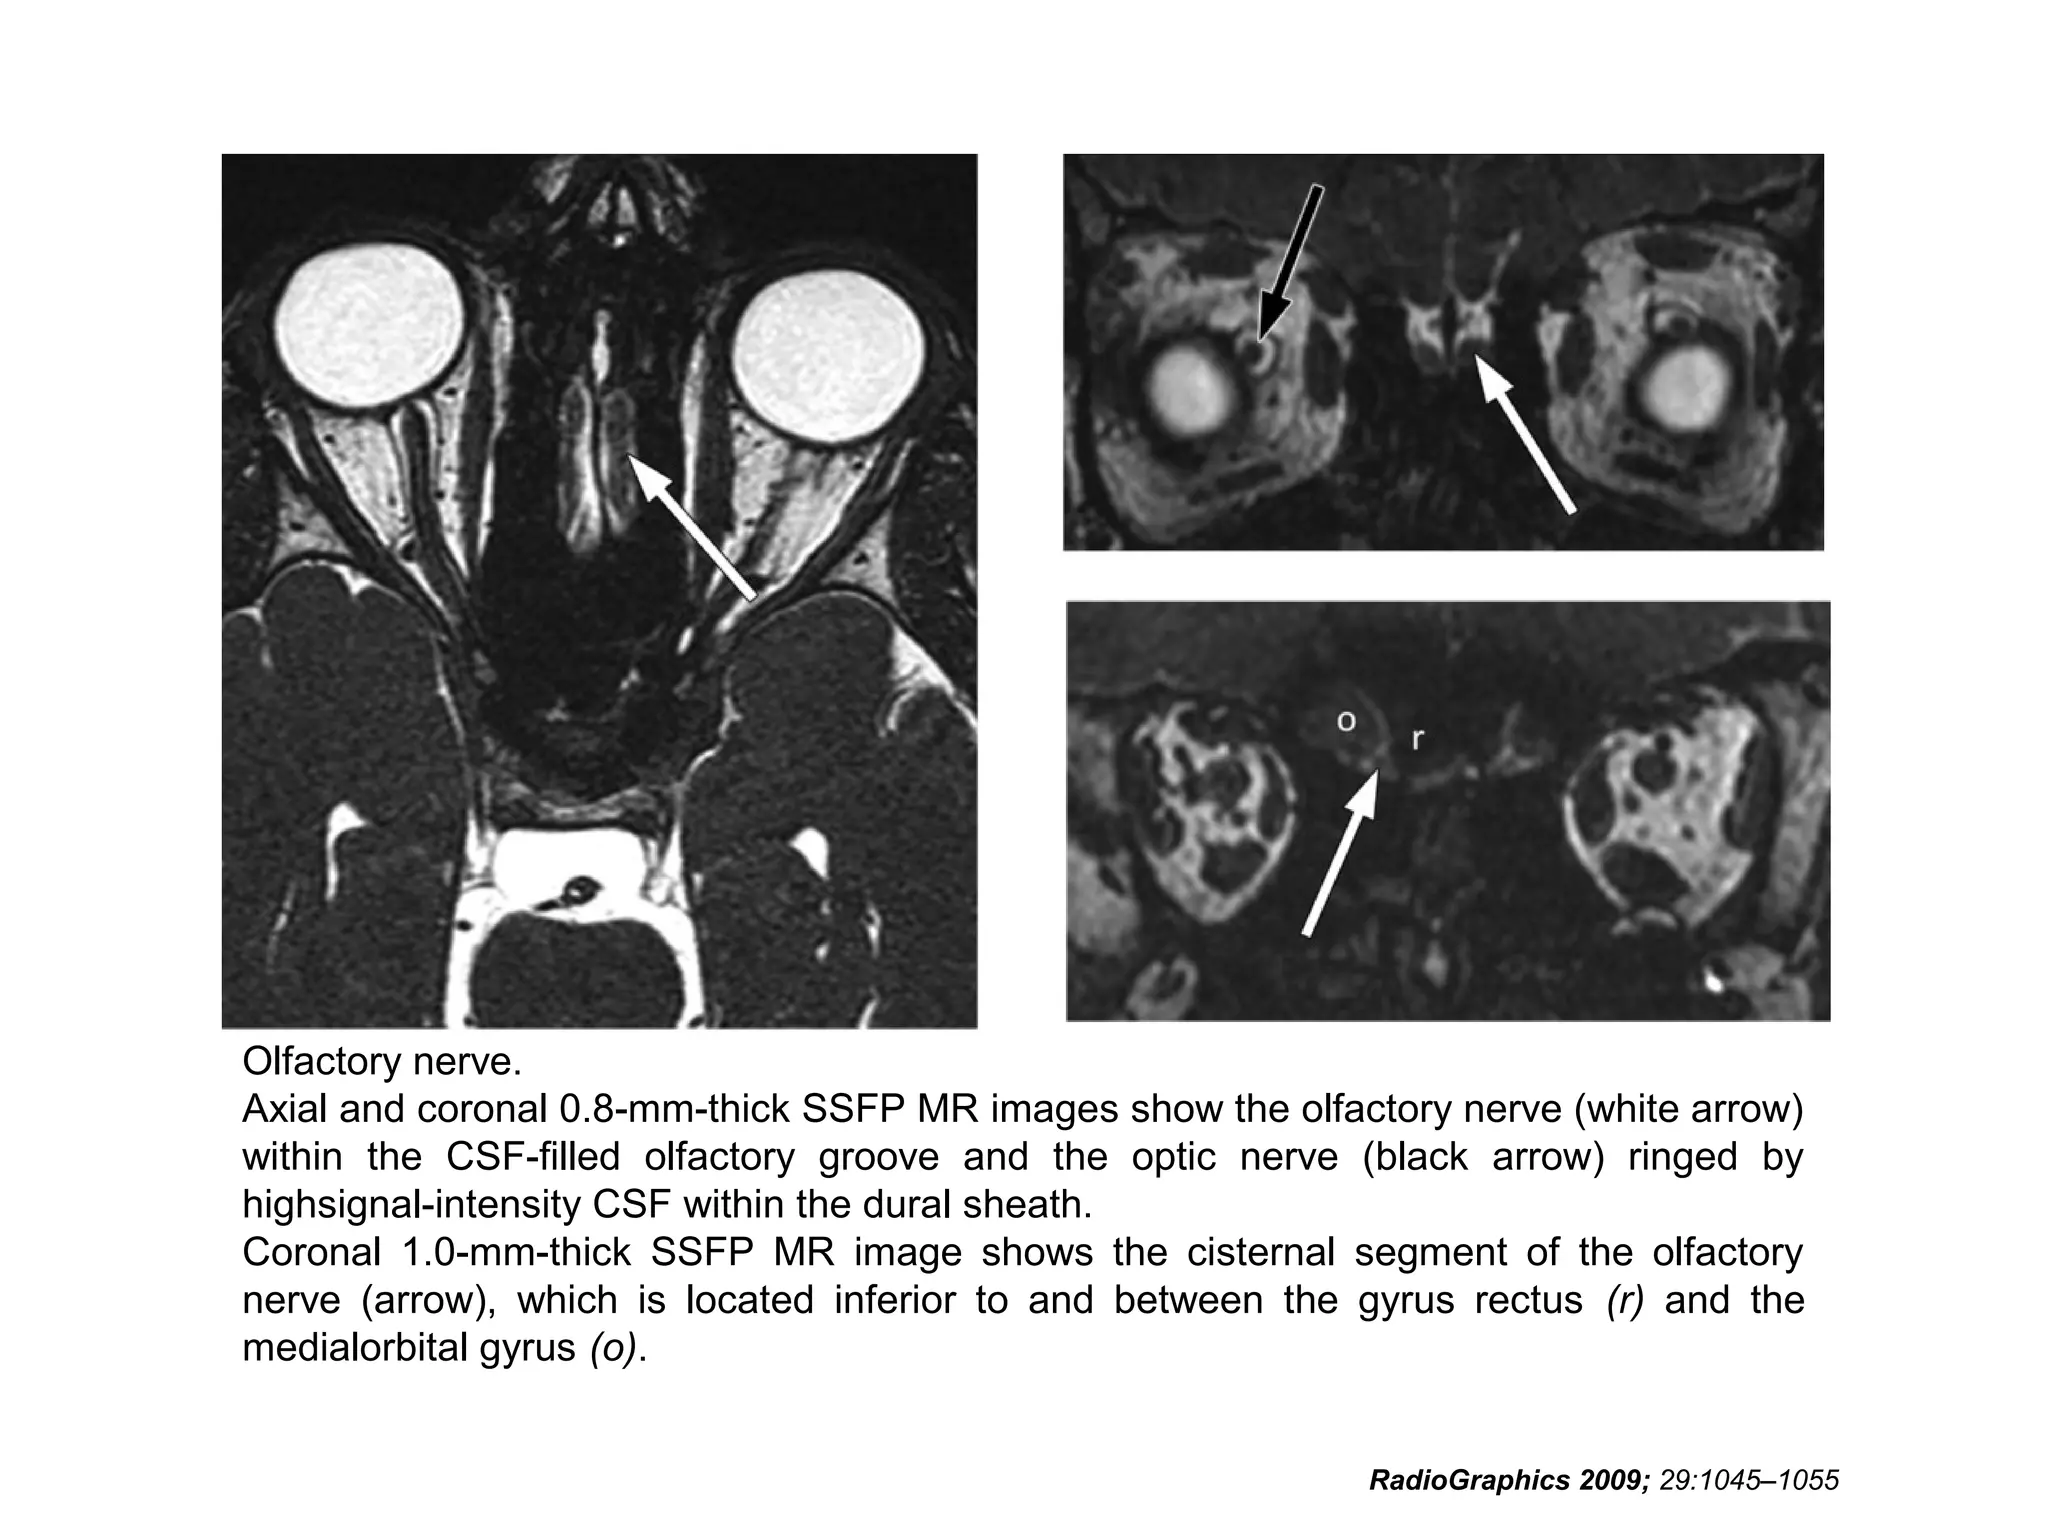

• Unlike most cranial nerves, the olfactory nerve consists

of white-matter tracts and is not surrounded by Schwann

cells

• The neurosensory cells for smell reside in the olfactory

epithelium along the roof of the nasal cavity

• The axons of these cells extend through the cribriform

plate of the ethmoid bone into the olfactory bulb at the

anterior end of the olfactory nerve

• The nerve then courses posteriorly through the anterior

cranial fossa in the olfactory groove

• Posterior to the olfactory groove, the cisternal segment

of the nerve runs below and between the gyrus rectus

and the medial orbital gyrus

• These secondary axons in the olfactory nerve

eventually terminate in the inferomedial temporal

lobe, uncus and entorhinal cortex

• To avoid confusing the olfactory nerve with the

gyrus rectus on axial images, it is important to

remember that the olfactory nerve is situated

deep in the olfactory groove, inferior to the gyrus

rectus

• Coronal images are easiest to interpret because

the nerves are seen in cross section

Olfactory nerve.

Axial and coronal 0.8-mm-thick SSFP MR images show the olfactory nerve (white arrow)

within the CSF-filled olfactory groove and the optic nerve (black arrow) ringed by

highsignal-intensity CSF within the dural sheath.

Coronal 1.0-mm-thick SSFP MR image shows the cisternal segment of the olfactory

nerve (arrow), which is located inferior to and between the gyrus rectus (r) and the

medialorbital gyrus (o).

RadioGraphics 2009; 29:1045–1055